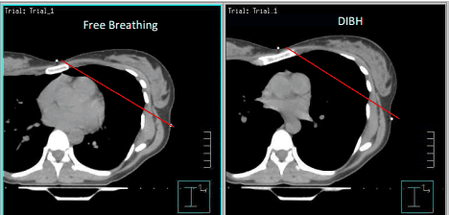

For some patients — especially those with left-sided breast cancer or with tumors in organs in motion (e.g., lung, liver, pancreas) — taking and holding a deep breath moves critical organs farther from the treatment area or fixes a tumor that is typically in motion. With DIBH, your breathing is monitored in real time, and the radiation beam pauses if you fall outside the safe range. Your care team will create and compare treatment plans to determine whether DIBH is right for you.